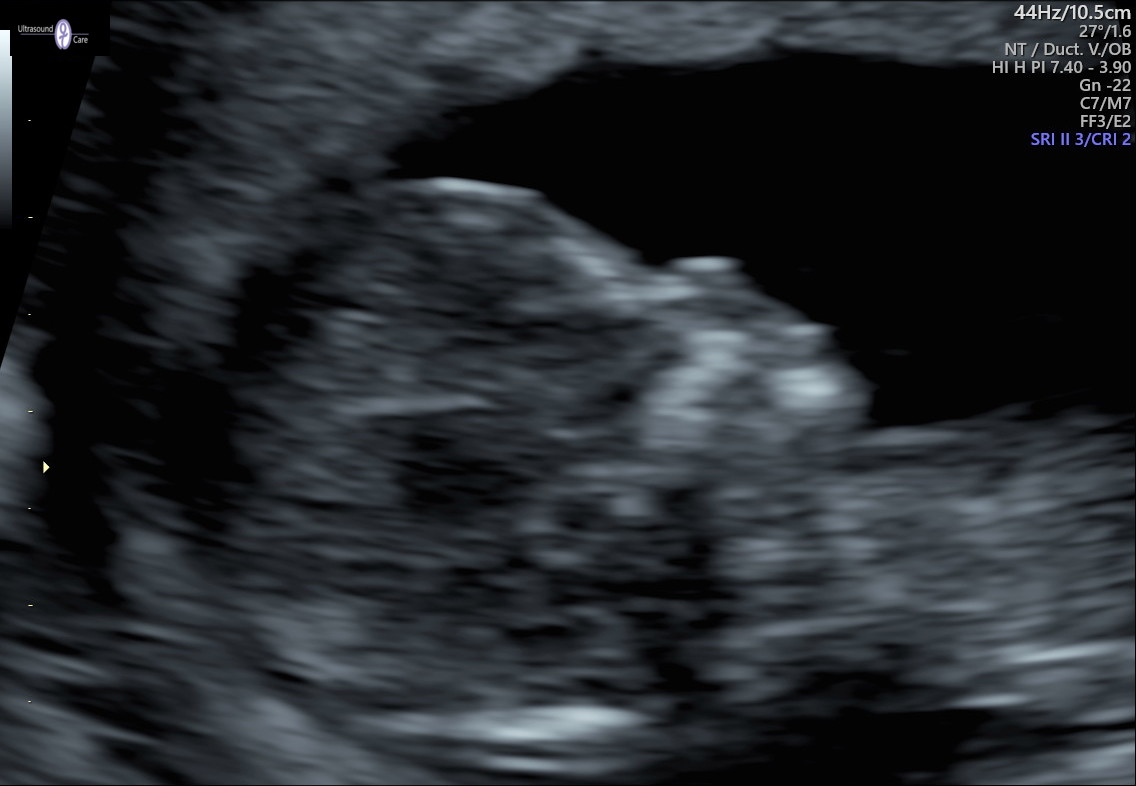

Any nub or skull guesses? The scan was done at 12 weeks 4 days.

ooh, I think that may be a boy on nub!!!